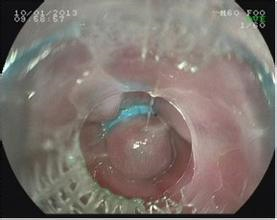

直腸類(lèi)癌內鏡下粘膜切除術(shù)